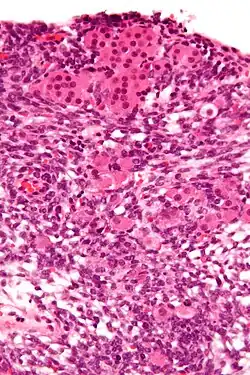

| Micrograph of a Sertoli–Leydig cell tumour. The Leydig cells have abundant eosinophilic or light pink cytoplasm. The Sertoli cells have a pale/clear cytoplasm. H&E stain. | |

The tumour is subdivided into many different subtypes. The most typical is composed of tubules lined by Sertoli cells and interstitial clusters of Leydig cells.